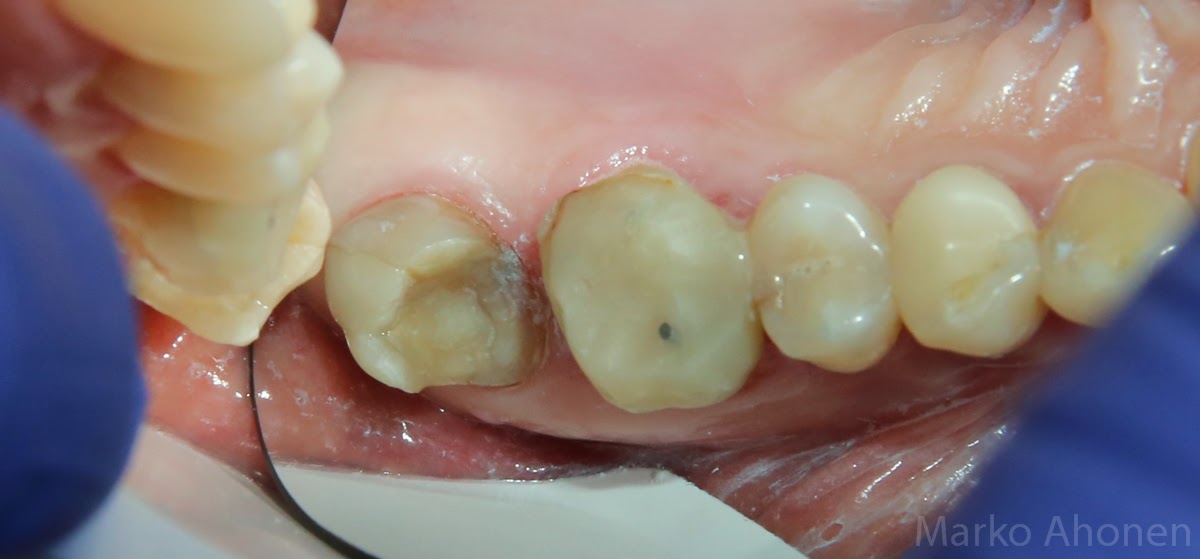

Potilaan kaksi takimmasta poskihammasta on jouduttu juurihoitamaan ja päälle on tehty muovikruunut. Takimmaisessa hampaassa muovi on lohjennut ja etummainen molaari kerää ruokaa sekä on vain osittain purennassa.